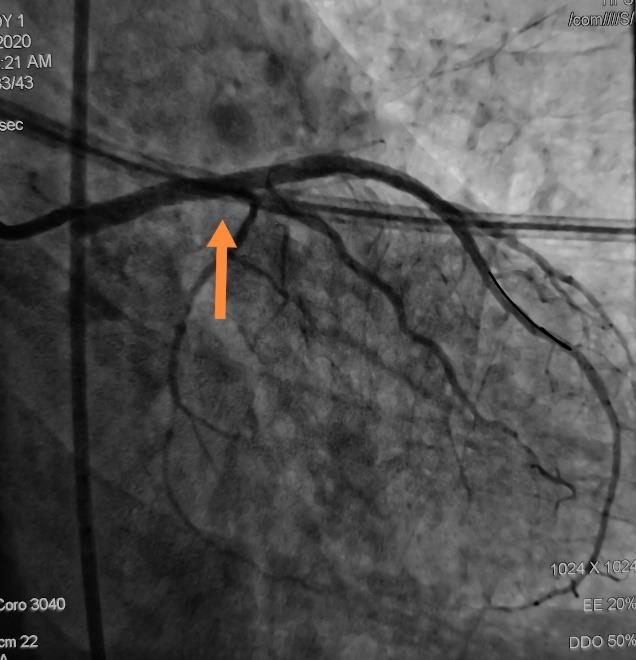

冠脉动脉重度狭窄支架植入术前术后DSA

心内科介入团队为该患者先行冠脉造影提示左侧冠状动脉主干重度狭窄,先行支架植入术。然后,神经介入团队行全脑血管造影术,提示左侧椎动脉重度狭窄,遂行椎动脉支架植入术。术后患者胸闷、胸痛症状消失,头晕症状改善,目前已康复出院。